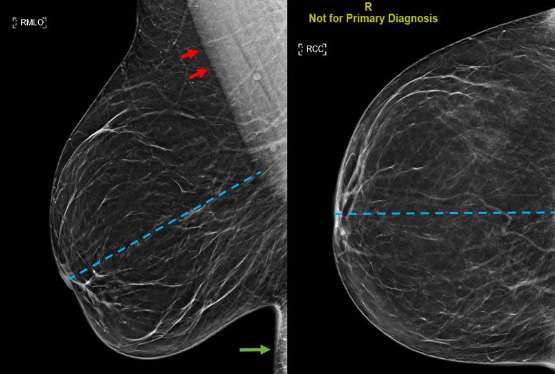

The standard mammographic views are the mediolateral oblique (MLO) and craniocaudal (CC) view. Obtaining at least two views of the breast allows for more breast tissue to be imaged and therefore offers a more comprehensive screening exam. Two views allows for better localization of underlying abnormalities that cannot be deciphered on a single view alone. It is important for the technologist to attempt to obtain views of the breast with the nipple in profile, ideally in both views, but in at least a single view to follow guidelines and to allow for adequate visualization of the breast tissue, particularly the subareolar region. The posterior nipple line (PNL), a line drawn at a 45 degree angle from the nipple towards the anterior aspect of the pectoralis on the mediolateral oblique view, is used to assess adequate imaging quality (Figure 1).4

A good mediolateral oblique (MLO) view provides visualization of the greatest amount of breast tissue, including the posterior breast and axillary region (Figure 1). When obtaining an MLO image, the breast is placed on the image receptor which lies parallel to the pectoralis muscle. The compression paddle then compresses the breast from a superomedial direction. In order to determine whether acquisition technique is adequate, it is important to assess three factors: the presence and position of pectoralis muscle, the posterior nipple line (PNL), and the inframammary fold.3

Ideally the margins of the pectoralis muscle appear as straight lines or convex curves, which implies breast tissue has been sufficiently pulled forward. The posterior nipple line should be able to intersect the pectoralis muscle at a perpendicular angle. The inframammary fold (IMF) is the most inferior portion of the breast which intersects the chest wall and should be included in the MLO image. Inclusion of the IMF promotes detection of masses that may be located in this most inferior aspect of the breast.

In the ideal craniocaudal view, the nipple should be positioned midline and the length of the PNL should be within 1 cm from that of the MLO view (Figure 1). The image receptor is positioned beneath the breast and compression is applied superiorly. When positioned correctly, the craniocaudal view has the advantage of showing the deep medial breast tissue which is often excluded on the mediolateral oblique view. Thus, it is imperative to ensure adequate inclusion of the deep medial breast in the CC view to detect masses that are otherwise excluded in MLO views (Figure 2).